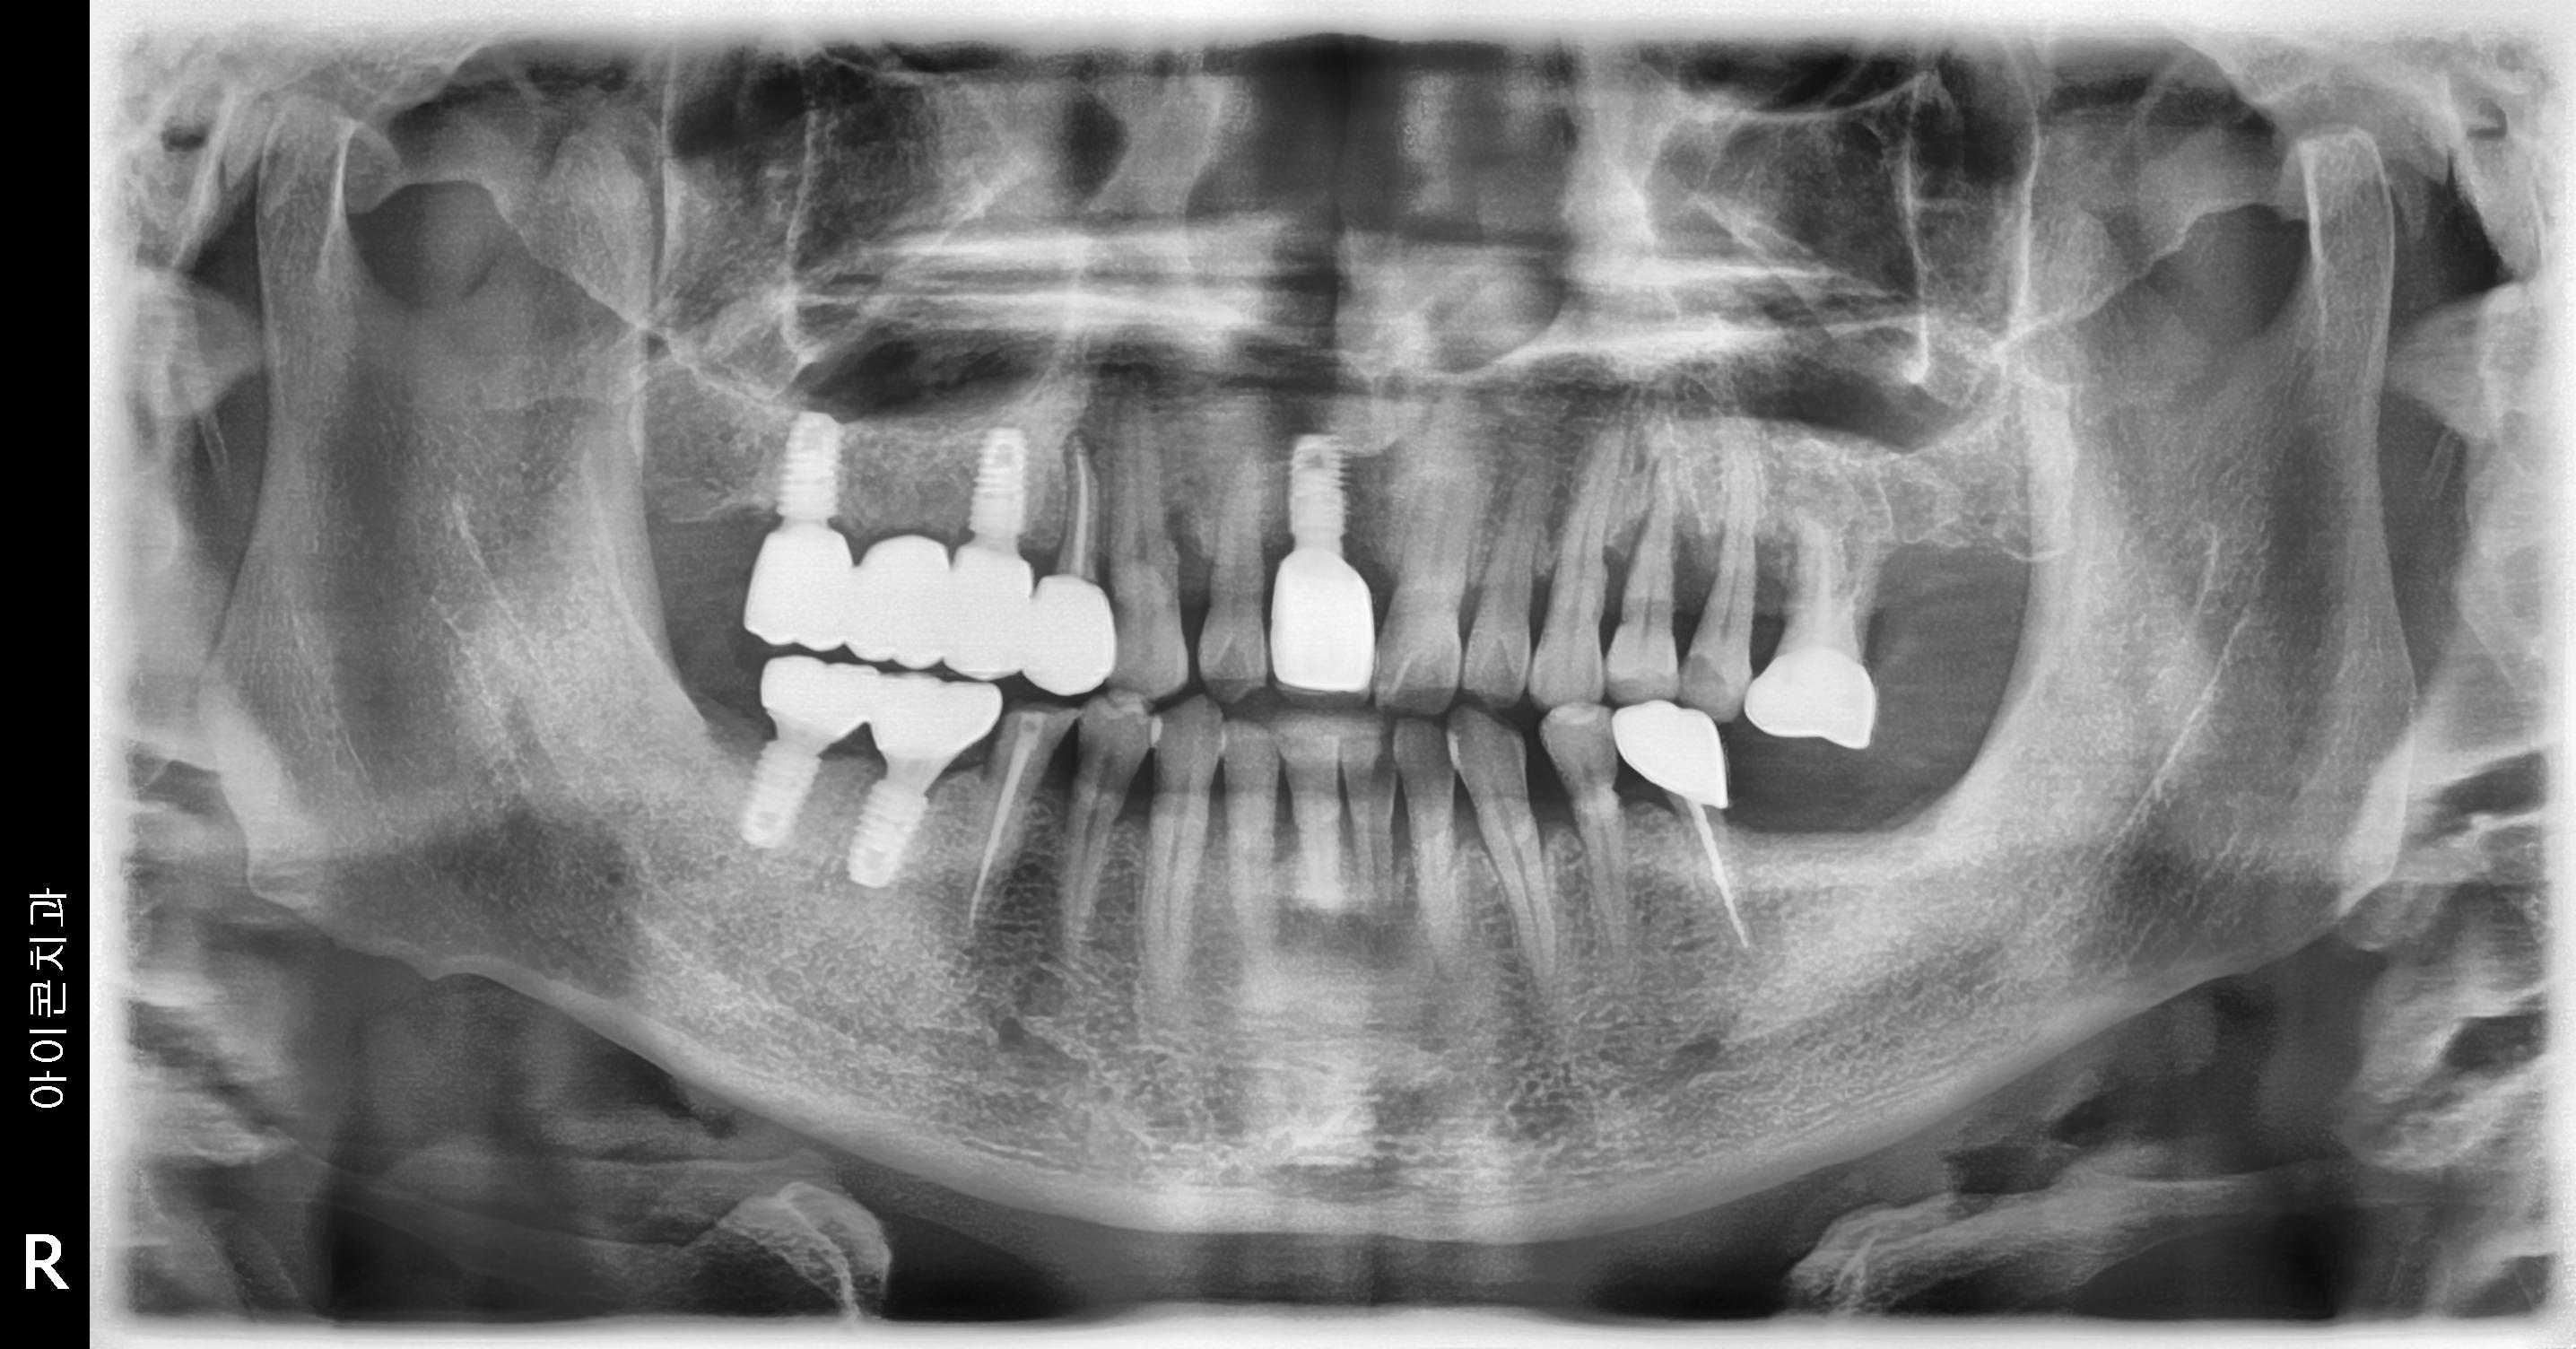

수술 전

수술 후

우측 임플란트 식립 사례

전후사진